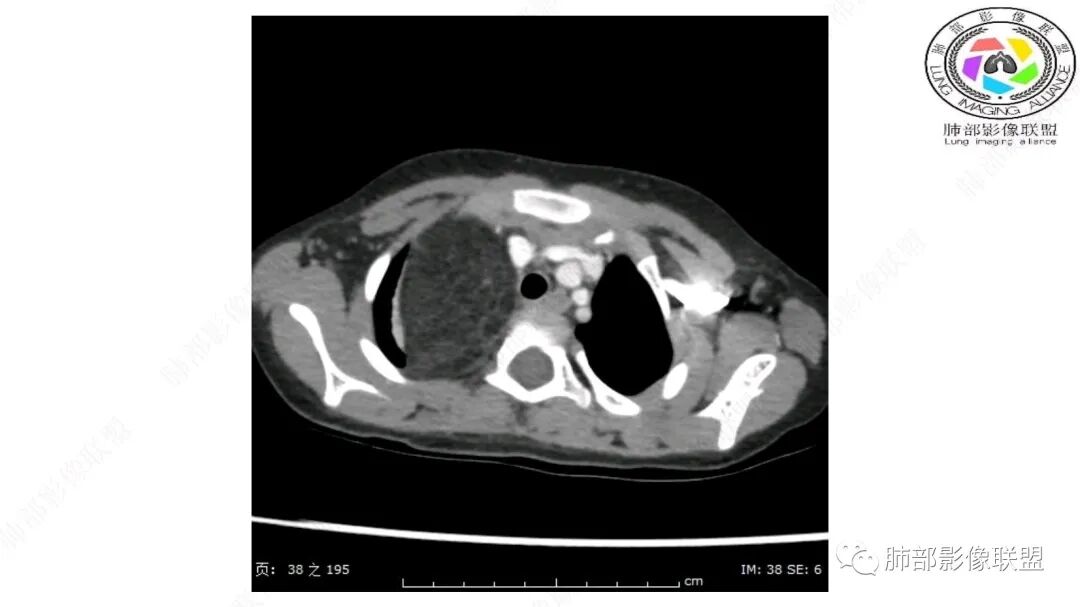

右上纵隔混杂密度肿块,边缘光整,与纵隔分界清,其内多发脂肪密度,增强无明显强化,其内血管穿行,考虑纵隔脂肪母细胞瘤,鉴别畸胎瘤,脂肪肉瘤。

三岁小儿,右侧纵隔巨大脂肪密度肿块,肺动脉穿行其中,密度欠均匀,未见明确实性成分,纵隔脂肪母细胞瘤,冬眠瘤鉴别纵隔脂肪增多症(多弥漫对称)。

患儿3岁 咳嗽检查发现纵隔占位。右肺上叶受压表现,占位以脂肪组织密度为主,似见分隔,首先考虑为脂肪母细胞瘤,鉴别脂肪瘤,畸胎瘤。

第一个问题:定位:肺内?纵隔?

病灶属于交界区,主体位于肺内,占位效应明显,前方突入胸壁,胸腺受压变形,胸膜显示欠清楚;病灶包绕上叶肺动脉;似乎有体动脉供血。符合肺内的点:包绕上叶肺动脉分支;符合纵隔的点:前方似乎突入胸壁,与胸腺关系比较密切,但是与上腔静脉的关系提示病灶不支持纵隔来源,前纵隔的常规会将上腔静脉受压后移、外移,这是不符合的。

从这个角度符合肺内的,有一点不太踏实的是:似乎突入前胸壁。